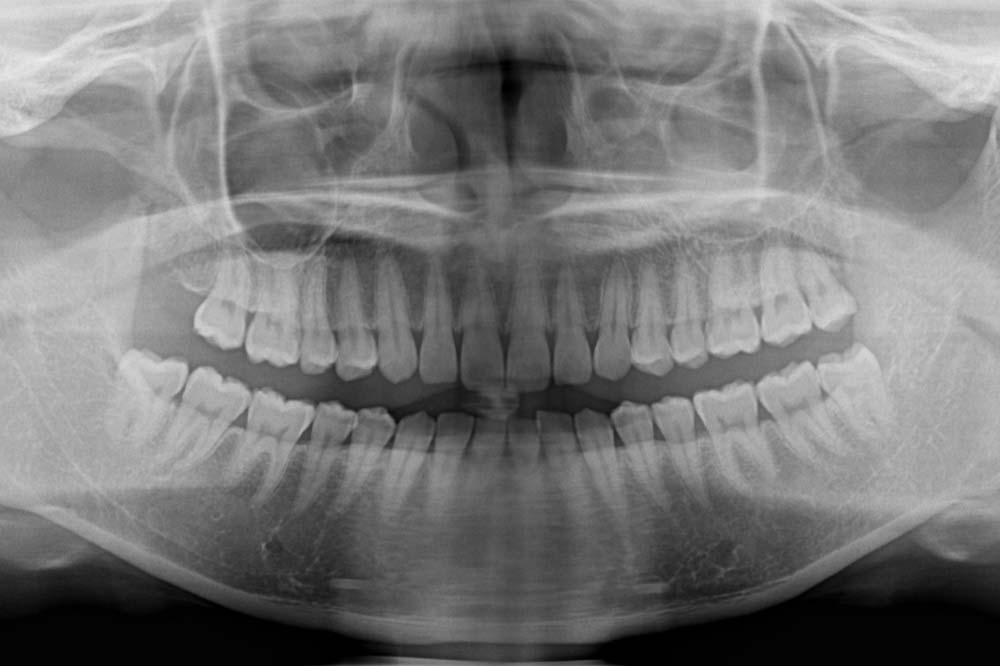

まずはレントゲンを撮影し、ご自身の親知らずの状態を確認することが大切です。

まずはレントゲンを撮影しご自身の親知らずの状態を確認することが大切です。

まずはレントゲン撮影や歯周病検査を行い、ご自身の状態を確認することが大切です。